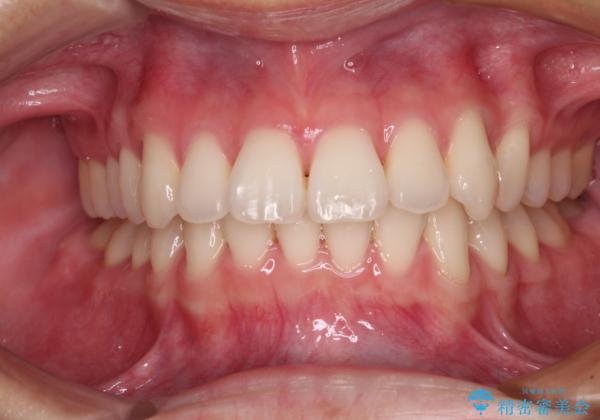

- 20代女性

- 矯正装置

- 治療期間

- 1年6ヶ月

クロスバイト改善中には歯髄壊死を起こすリスクがあるため、神経に問題がないか確認しながら治療を進めて行く必要があります。

思っていたよりも早くクロスバイトは改善され、歯髄壊死に至ることなく、無事に治療を終えることができました。